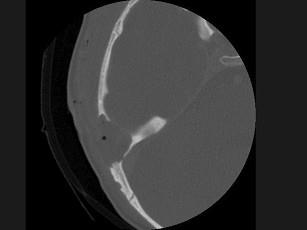

女性,17岁,右耳乳突区隐痛,右耳后乳突区出现包块,逐渐增大,CT检查如图所示,请选择最可能的 ( )